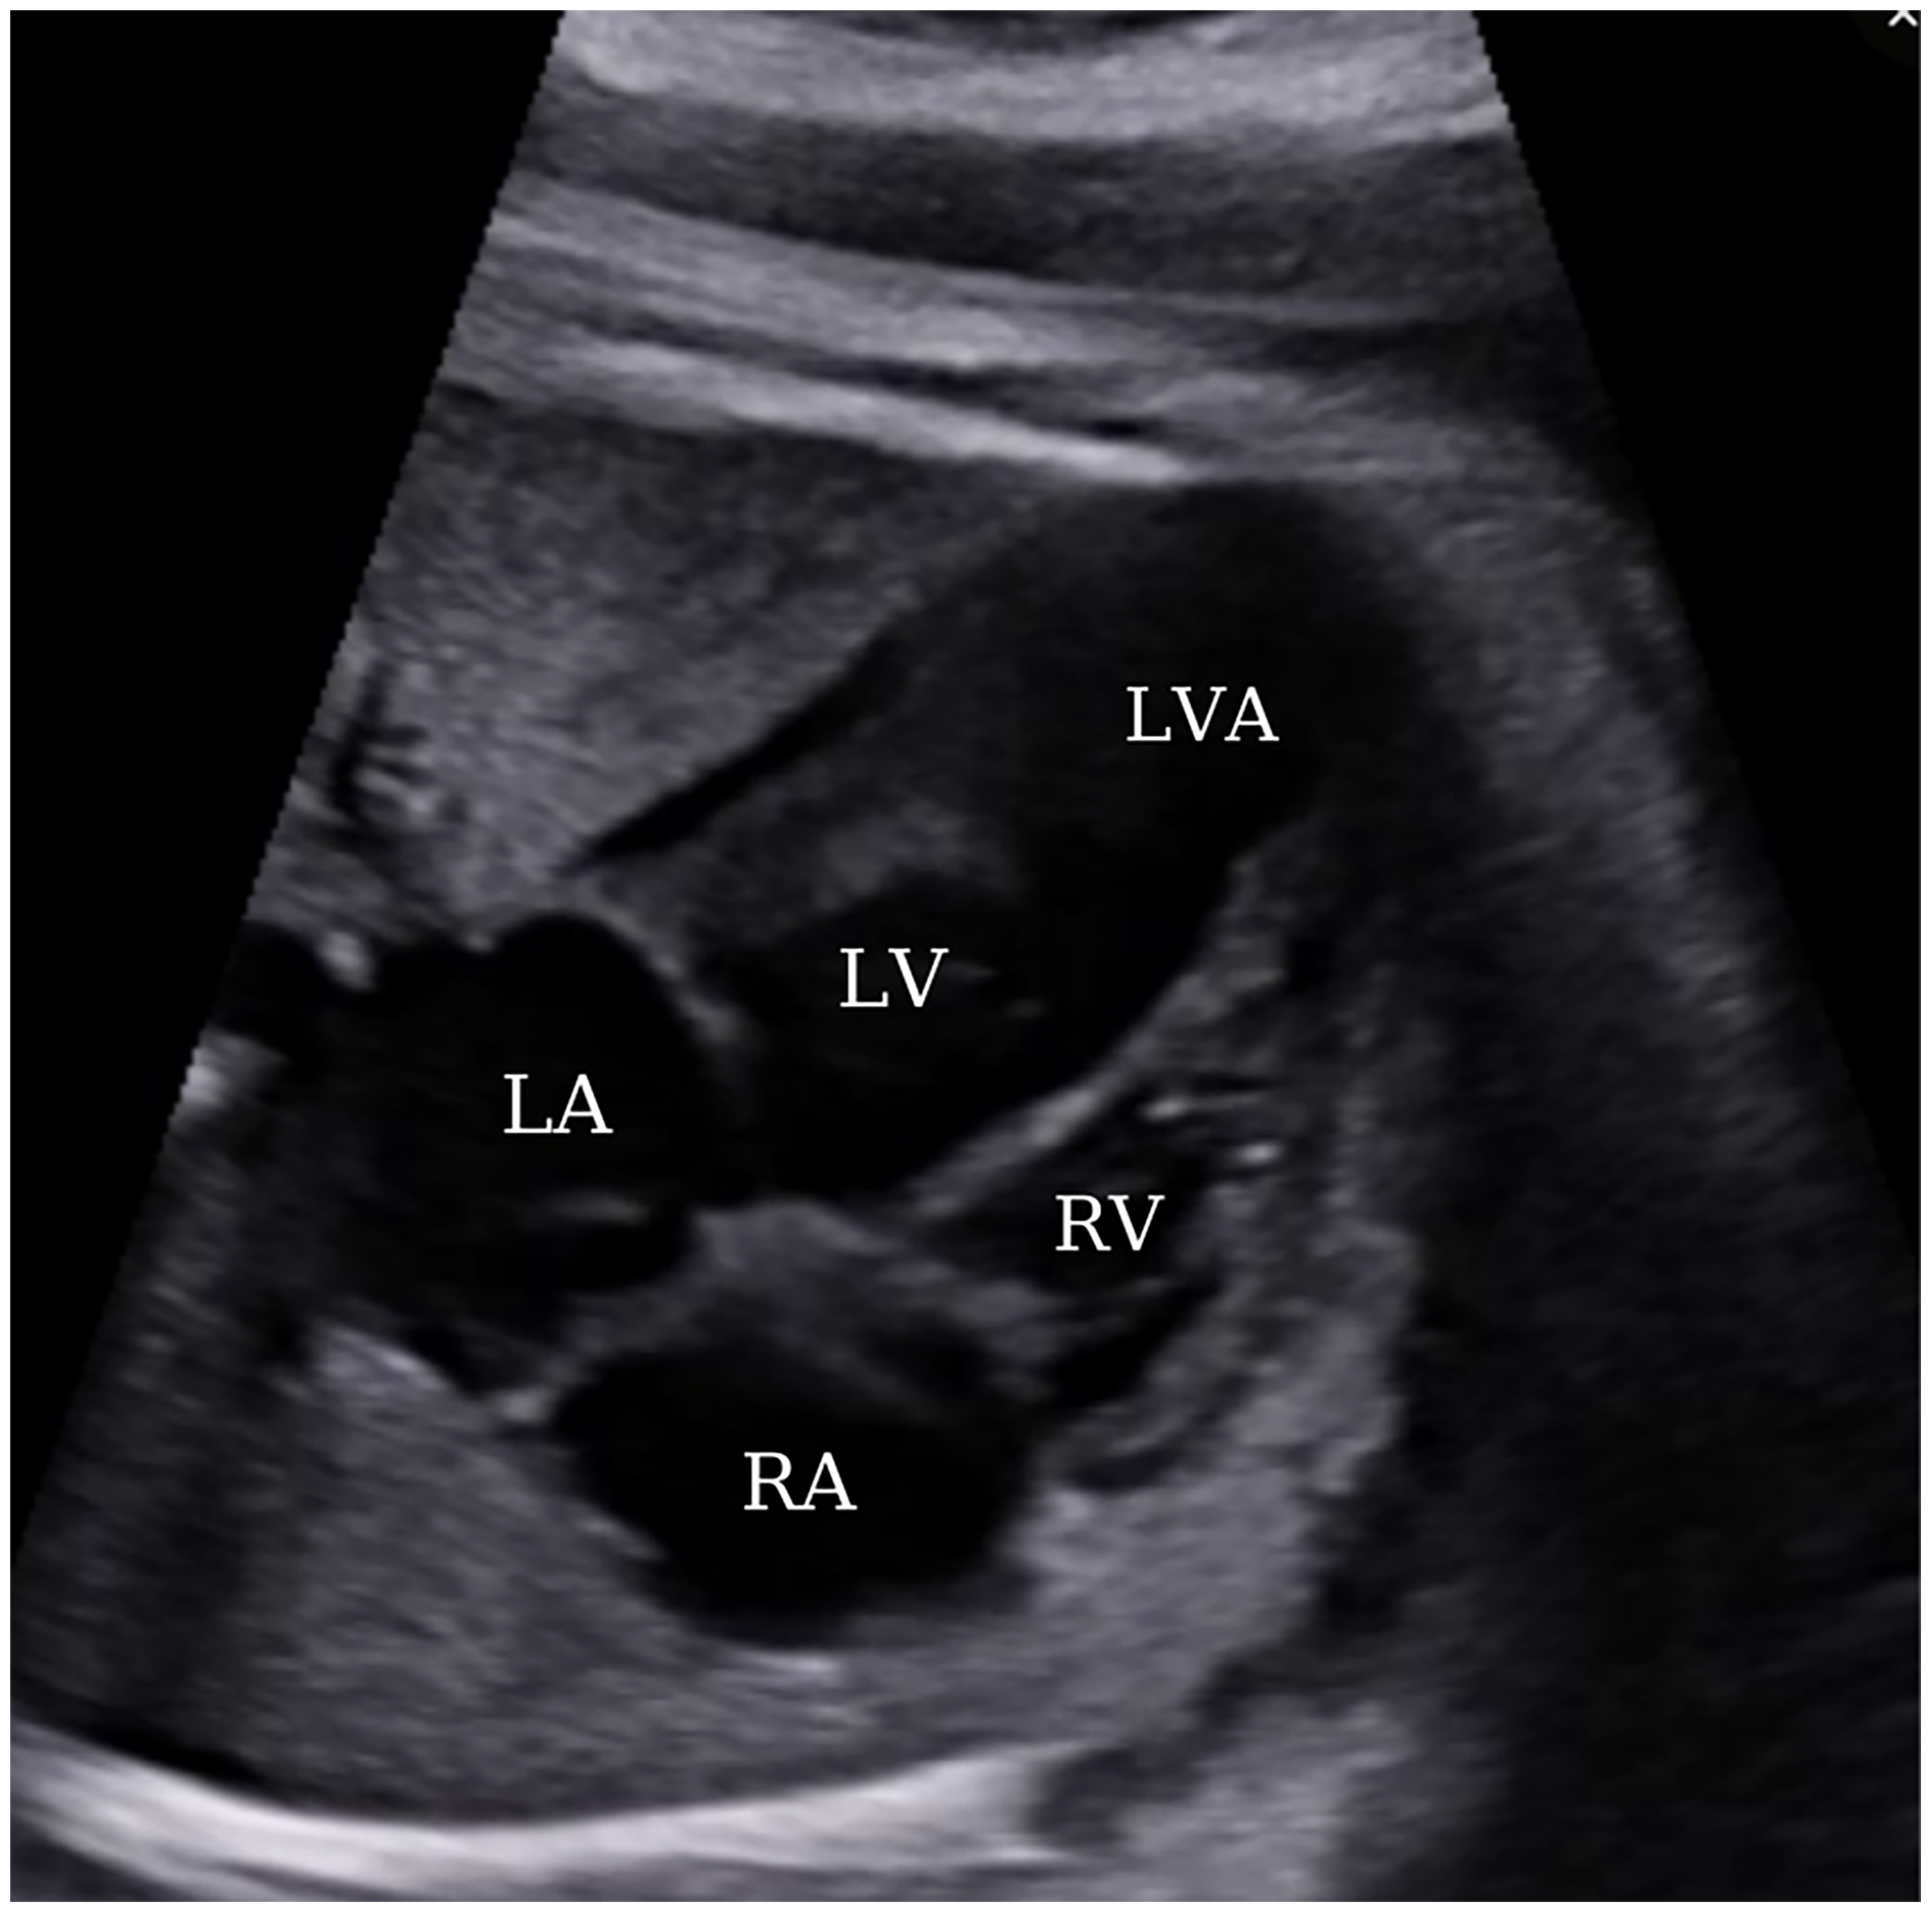

Throughout the course of the pregnancy, a biweekly series of ultrasonography was conducted with the primary objective of identifying antenatal adverse events, including fetal arrhythmia, pericardial effusion, aneurysm rupture, or fetal loss. Furthermore, a meticulous examination of fetal biometric measurements, aneurysm dimensions, and cardiothoracic ratio to assess mass effect on the lungs, and the determination of the presence of polyhydramnios and oligohydramnios was undertaken during ultrasound follow-ups to ascertain the potential occurrence of fetal growth restriction. In the later stages of pregnancy, the dimensions of the aneurysm increased to 14 mm × 16 mm; however, no additional unfavorable findings, such as pericardial effusion or aneurysm rupture, were observed (Fig. 4).

Figure 4: A view from a four-chamber section displaying an apically located left ventricular aneurysm at 35 weeks of gestation. LA, left atrium; LV, left ventricle; RA, right atrium; RV, right ventricle; LVA, left ventricular aneurysm